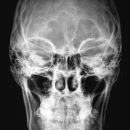

Schädel a.-p.

Symmetrische Abbildung beider Schädelhälften, Nasenscheidewand streng in der Mitte. Die Felsenbeine stellen sich im unteren bis mittleren Drittel der Orbita da. Felsbeinspitzen projizieren sich in die Mitte der Orbita oder eher etwas oberhalb davon.